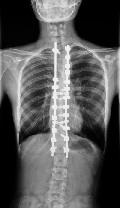

当院では、脊椎、腰、股関節の形体・配列の評価を行うことができるX線撮影装置「sterEOS(イオス)イメージングシステム」を県内で初めて(国内で3機目)導入しており、この装置では、通常のX線撮影と比較して50%、CT撮影と比較して95%放射線量を低減した撮影ができます。また、マイクロドーズモードを使用することで、経過観察の小児や、経過治療中に頻回の撮影を必要とする疾患の患者さんに対し、さらなる放射線被ばく低減を可能にします。

sterEOSイメージングシステム

このEOSの画像検査により、低被爆で弯曲のタイプ・進行具合を確実に診断出来るので、治療方針の決定に大いに役立ちます。